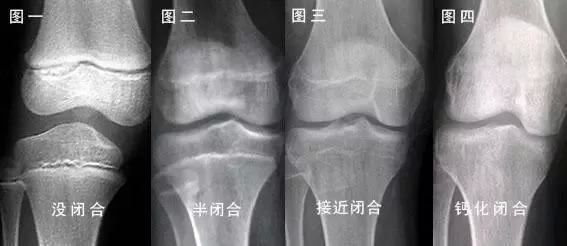

图片来源:网络

闭合前的骺板是一条透亮的区带,而闭合后透亮区消失,与旁边的骨骺融为一体。

所以,如果拍出来的 X 光片里是透亮透亮的,那就让人羡慕嫉妒恨了!

这说明下肢很给面子,还有长高的可能。